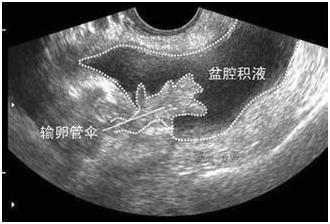

受精卵在子宫体腔以外着床的现象称为异位妊娠,最常见的是输卵管妊娠。当输卵管妊娠流产或破裂,就会输卵管壁破裂出血,血液聚积在子宫直肠陷凹,进而形成盆腔积液。从后穹窿可以抽吸出不凝固血液。